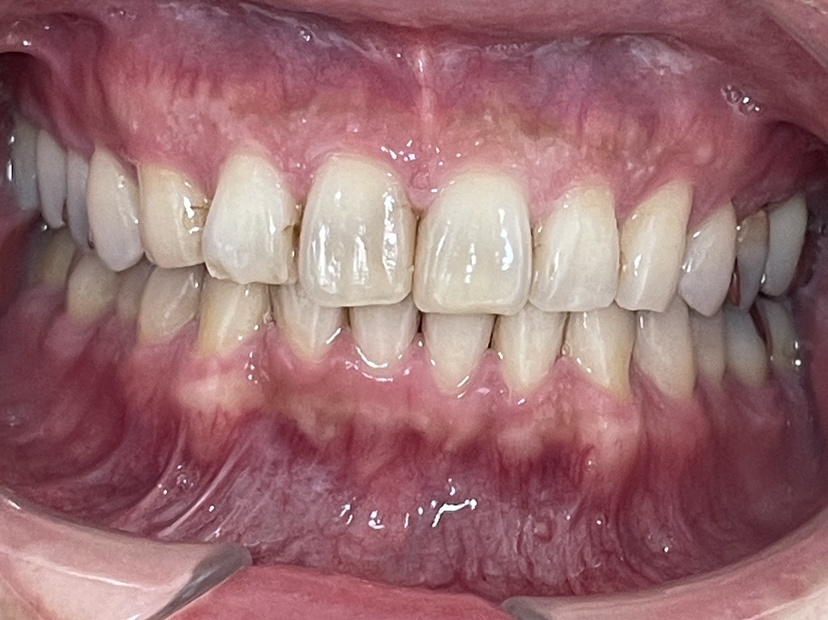

拝見したところ、左下の前歯(中切歯/1番)は歯の並び「歯列」から前に飛び出し、デコボコに並ぶ「叢生(そうせい)」が見られました。

また、上下の歯を噛み合わせた時に、上の前歯が覆いかぶさって下の前歯が見えなくなる深い噛み合わせ「過蓋咬合」でした。

前に1本出ていた前歯は、しっかり歯列におさまりきれいな歯並びになりました。

過蓋咬合も改善し、正しい位置で噛み合わせられるようになりました。